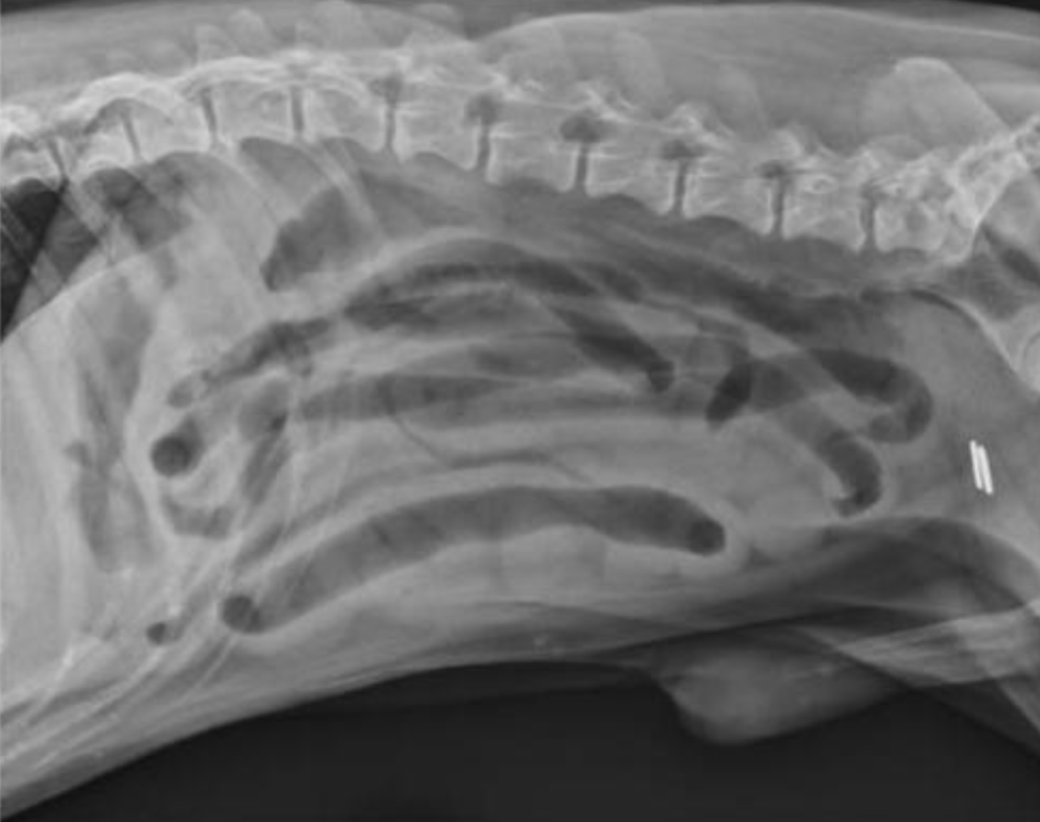

Un Border Collie mâle stérilisé de 9 ans est présenté en consultation pour des vomissements évoluant depuis 48 heures, sans amélioration malgré un traitement symptomatique mis en place initialement (antiémétiques et pansement digestif).

L’animal est abattu et présente une douleur abdominale modérée à la palpation. La température est normale.

Des radiographies abdominales sont réalisées.

L’examen radiographique met en évidence :

- La présence de deux populations d’anses intestinales grêles de diamètres différents :

- certaines vides

- d’autres dilatées par du gaz et du liquide

Cette distribution est évocatrice d’un iléus mécanique

- Un contenu digestif grêle atypique, visible à droite de la ligne médiane au niveau de L5–L6, caractérisé par un aspect réticulé mêlant gaz et opacité tissulaire

L’aspect est compatible avec la présence d’un corps étranger intraluminal

- Le côlon est modérément dilaté par du gaz

- Une spondylose déformante marquée entre L6 et S1, ainsi qu’entre L6 et L7

Les images sont compatibles avec une obstruction mécanique de l’intestin grêle, très probablement secondaire à la présence d’un corps étranger intraluminal, dont l’aspect est fortement suspect d’un trognon d’épi de maïs.

La spondylose lombo-sacrée observée correspond à une lésion dégénérative chronique incidente, sans lien avec le motif de consultation.

Chez un chien présentant des troubles digestifs aigus, l’identification radiographique de deux populations d’anses grêles (certaines vides, d’autres dilatées) constitue un argument fort en faveur d’une obstruction mécanique digestive. Ce pattern est plus spécifique qu’une dilatation diffuse des anses intestinales, plus classiquement observée lors d’iléus paralytique.